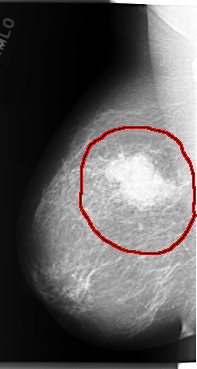

C_0066_1.RIGHT_MLO

FILE: C_0066_1.RIGHT_MLO.OVERLAY

TOTAL_ABNORMALITIES 1

ABNORMALITY 1

LESION_TYPE CALCIFICATION TYPE PLEOMORPHIC DISTRIBUTION CLUSTERED

LESION_TYPE MASS SHAPE LOBULATED MARGINS MICROLOBULATED

ASSESSMENT 5

SUBTLETY 5

PATHOLOGY MALIGNANT

TOTAL_OUTLINES 1

BOUNDARY